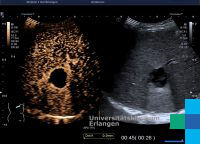

Die Symptome eines Leberabszesses sind meist hohes Fieber, Leberdruckschmerz, Übelkeit und Erbrechen, Gelbsucht und Anämie. Die Diagnose wird mittels Ultraschalluntersuchung und einer CT-Aufnahme gesichert. Die Therapie erfolgt medikamentös (durch hochdosierte Antibiotikagaben), durch eine perkutane Drainage oder durch chirurgische Entfernung der Abszesshöhle eventuell durch eine Segmentresektion. Als Komplikationen eines Leberabszesses gelten eine Sepsis oder Ruptur der Abszesshöhle mit Durchbruch in die freie Bauchhöhle und nachfolgender Bauchfellentzündung.